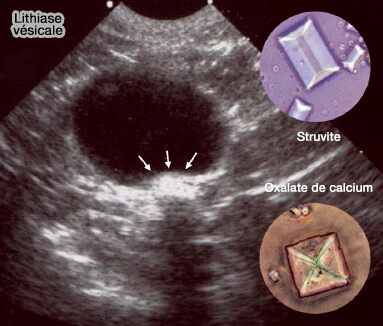

Lithiase vésicale

(Figure : vetopsy.fr)

1. Votre vétérinaire doit d'abord éliminer toutes les causes somatiques et en particulier, les MBAU (Maladie du Bas Appareil Urinaire), dont les étiologies sont variées, en particulier les lithiases, i.e. calculs urinaires !